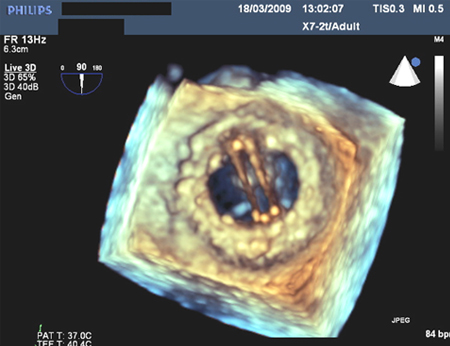

Prosthetic mitral valve with intermittent mitral regurgitation

From the collection of Prakash P. Punjabi

See this image in context in the following section/s: